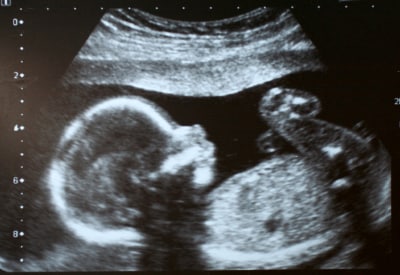

CT is one of the two technologies that utilize ionizing radiation to create a picture of what is going on inside the body. At its simplest, a CT scan is an x-ray slice of the body. Slices are repeated along the area of interest, although for performance reasons multiple slice transmitters/receivers are typically grouped next to each other. The body can also be moved during exposure in order to create a “spiral” image that can be unwound into slices or a 3D view (see Figure 1).

Figure 1: CT scan of the human brain.